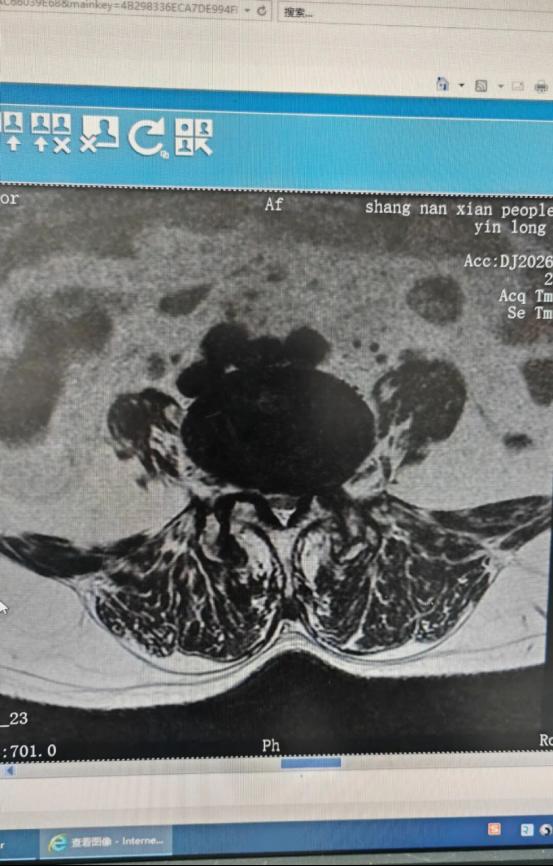

术前MRI显示:椎管狭窄